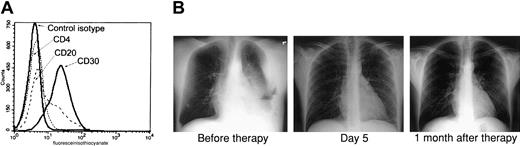

Because the combination of AZT and IFN-α exhibited a potent proapoptotic effect in PEL lines and both of these antiviral agents have been used extensively in AIDS patients, we developed a clinical protocol for this relatively rare disease. Recently an HIV-positive man, 35 years of age, presented to the emergency room complaining of shortness of breath. His absolute CD4+ T-cell count was 222/mm3 with an undetectable HIV load, and he had not taken any antiretroviral medications for several months before admission. Chest x-rays revealed a large left-sided pleural effusion and fluid accumulation in the mediastinum. Examination of this pleural fluid revealed an anaplastic lymphoproliferative process, and flow cytometry performed on tumor cells demonstrated the typical phenotype of PEL: CD4−, CD20−, and CD30+ (Figure1A). Multiple analyses of tumor cells by polymerase chain reaction (PCR) repeatedly demonstrated the presence of HHV-8 and absence of EBV (data not shown). The patient was advised of his condition, and written informed consent was obtained for our clinical protocol, which uses twice-daily parenteral AZT 1.5 g and IFN-α 5 million units. No other antineoplastic, corticosteroid, or antiretroviral agents were administered. The patient had a remarkable response with resolution of his effusion within 5 days, as demonstrated by chest x-rays (Figure 1B) and computed tomography scan (not shown). Ten days after starting parenteral therapy, he was discharged on oral AZT 600 mg daily and subcutaneous IFN-α 5 million units daily. A repeated chest film performed on the patient one month after diagnosis was clear. He continued taking AZT and IFN-α only for an additional 2 months and then stopped taking antiviral agents, although he was seen 6 months later at our AIDS clinic and was symptom free.

(A) Primary tumor cells (BCLM) from an HHV-8+ PEL patient demonstrate typical phenotype of PEL. Surface expression of CD4, CD20, and CD30 on 1 × 106 cells from pleural fluid was determined by FACS analysis. (B) AZT and IFN-α induce remission in the PEL patient. Left: Chest x-ray of the same patient 2 days after diagnostic thoracentesis and before therapy with twice-daily parenteral AZT 1.5 g and IFN-α 5 million units. Middle: Chest x-ray 5 days after initiation of therapy. Right: Chest x-ray 1 month after therapy.

AZT and IFN-α induce remission in a PEL patient.